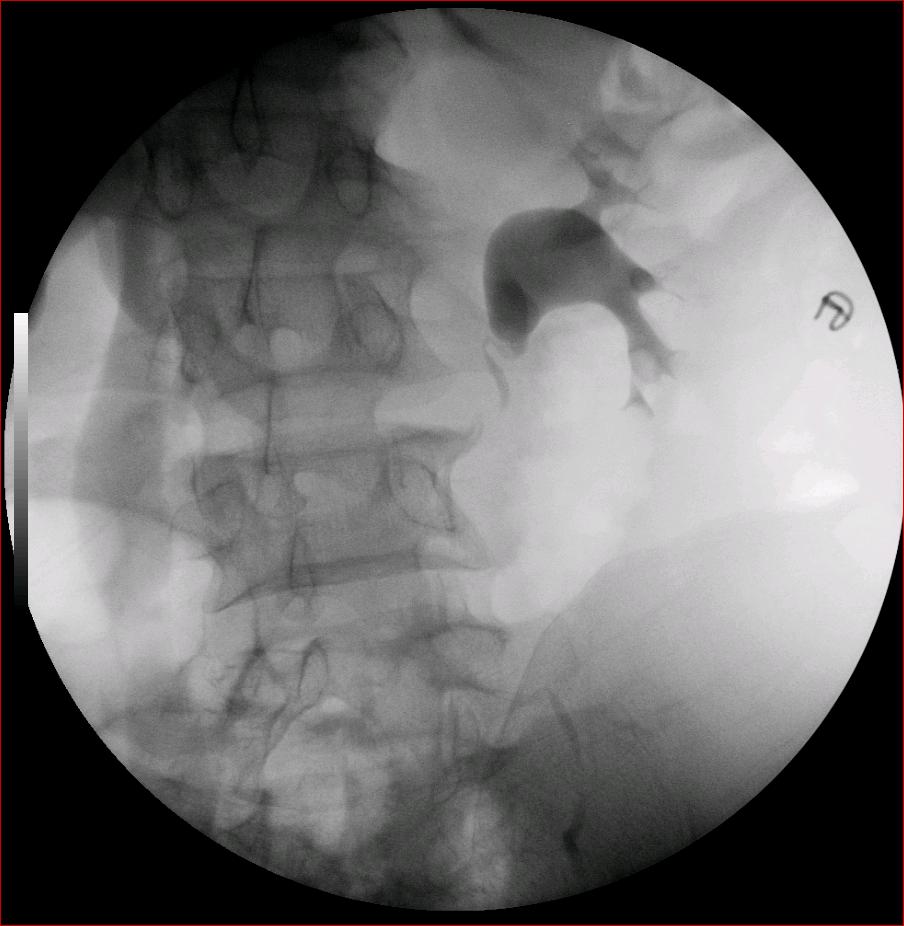

以下是引用luoxinjun在2008-2-18 15:54:00的发言:[br]右肾积水,右输尿管下端结石

以下是引用zhangxiangjun在2008-2-18 21:01:00的发言:[br]右输尿管盆段末端结石,继发其近端输尿管、右肾积水。

以下是引用hexue在2008-2-18 17:33:00的发言:[br]右输尿管下段结石并右肾及右输尿管积水扩张

以下是引用杀毒软件在2008-2-18 16:24:00的发言:[br]右输尿管下段结石,肾盂积水。